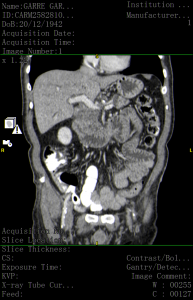

Caso 57

El TC de abdomen es una prueba de gran importancia a la hora de tomar decisiones en el tratamiento, sobre todo para valorar la posibilidad de cirugía. También resulta muy útil para conocer la extensión del tumor a órganos vecinos y la afectación o no de los ganglios linfáticos. Dura aproximadamente 20 – 30 minutos, y no provoca dolor. Aunque es necesario que la persona permanezca inmóvil sobre la camilla del escáner durante su realización.

Que te planteas como diagnostico mas probable?